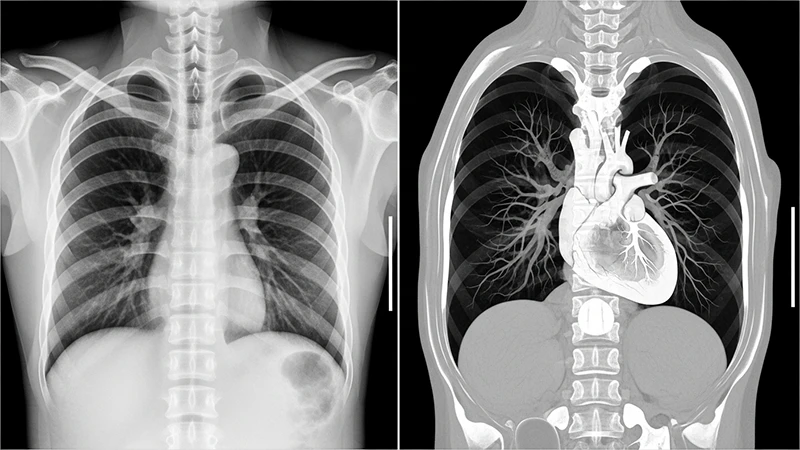

While a conventional X-ray provides a flat, two-dimensional view of the body, Computed Tomography (CT) represents a revolutionary leap forward. By combining X-ray technology with powerful computers, CT scanners produce detailed, cross-sectional images—or "slices"—of the body, allowing us to see inside with unprecedented clarity. It eliminates the overlapping of structures seen in standard radiography, providing a much clearer view of organs, bones, and soft tissues.

Side-by-side comparison showing a standard chest X-ray next to a detailed CT slice of the chest